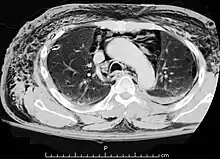

Pneumomediastino (do grego pneuma ar) ou enfisema mediastinal é uma presença anormal de ar entre os pulmões (no mediastino). Descrito pela primeira vez em 1819 por René Laennec.[1] A condição pode resultar de trauma físico ou outra lesão que cause que ruptura das vias respiratórias (como tráquea, laringe ou pulmões) ou da via digestiva (como esôfago e estômago) para a cavidade torácica.